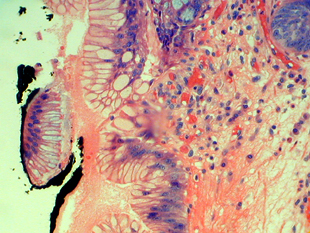

Metaplastic columnar epithelium underlying squamous epithelium

Use of proton-pump inhibitors may cause caudad migration of the squamo-columnar junction, or squamous islands may develop within the Barrett’s segment. In either case, Barrett’s metaplastic epithelium may still present underneath the squamous epithelium on the surface (squamous overgrowth). Because dysplasia and adenocarcinoma may develop within the metaplastic columnar epithelium underneath the squamous surface, the endoscopist must biopsy these squamous islands. Unfortunately, since no overlying columnar epithelium is present for evaluation (being completely replaced by squamous epithelium) the criterion of mucosal surface involvement by atypical epithelium cannot be used to make the diagnosis of dysplasia. We look for marked nuclear atypia in combination with architectural distortion before raising the possibility of dysplasia. We are hesitant to make the diagnosis of low-grade dysplasia based on the deep glands; but we think that a diagnosis of high-grade dysplasia can be rendered if the nuclear features (loss of nuclear polarity, hyperchromatism, pleomorphism) are consistent with high-grade dysplasia.

Metaplastic columnar epithelium adjacent to a squamous island

Frequently the columnar epithelium immediately adjacent (1 to 2 glands) to a squamous island displays atypical nuclear features that are present on the mucosal surface. We are hesitant to make the diagnosis of dysplasia in this context. We like to see the nuclear atypia involve the surface epithelium in areas several crypts away from the squamous island before making the diagnosis of dysplasia. The questions arises, "How far is far enough?" We believe that in Barrett’s esophagus negative for dysplasia, the epithelium on the mucosal surface should appear normal 2 or 3 glands away from the squamous island. Abnormal nuclear changes beyond this point probably indicate dysplasia.